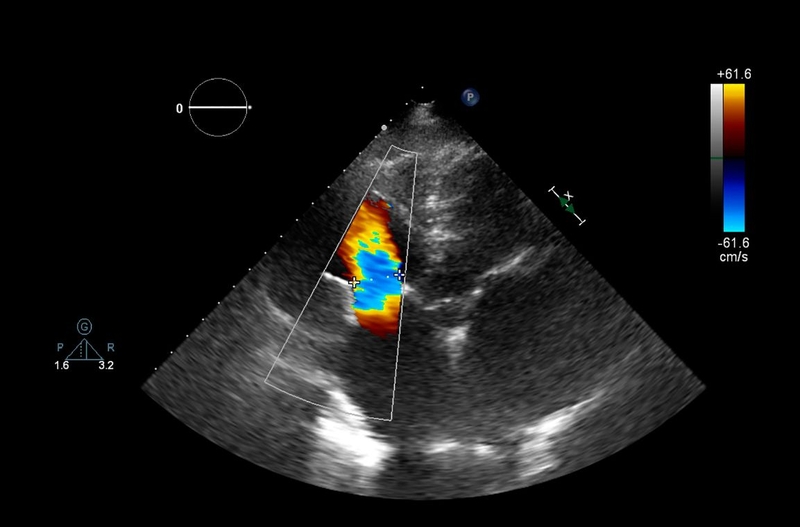

Để có các chỉ số quan trọng phục vụ cho mục đích đánh giá chức năng tim, các bác sĩ sẽ chỉ định thực hiện siêu âm tim. Siêu âm tim là kỹ thuật chẩn đoán hình ảnh tim không xâm lấn nhằm mục đích khảo sát chức năng, hình thái, huyết động học của tim (gồm buồng tim, màng ngoài tim, mạch máu lớn nối với tim, vách tim).

Các phương pháp chẩn đoán bệnh lý liên quan đến tim không ngừng phát triển. Siêu âm tim không phải kỹ thuật mới nhưng vẫn luôn là chỉ định đầu tay khi cần theo dõi sức khỏe tim mạch. Khi nghi ngờ các bất thường hay bệnh lý về tim, các bác sĩ vẫn thường chỉ định siêu âm tim đầu tiên sau đó mới đến các xét nghiệm bổ sung hoặc chuyên sâu khác. Siêu âm tim để có các chỉ số đánh giá chức năng của tim có các loại như:

Trong các cách đo chỉ số đánh giá chức năng của tim, siêu âm tim có vai trò vô cùng quan trọng. Đây là phương pháp khảo sát đơn giản, không xâm lấn, thực hiện nhanh chóng nhưng lại đưa ra kết quả chính xác có độ tin cậy cao. Siêu âm tim giúp bác sĩ có được các chỉ số cần thiết để đánh giá hình thái, chức năng, huyết động học của các mạch máu lớn nối với tim, màng ngoài tim, buồng tim, vách tim. Qua đó, bác sĩ có thể chẩn đoán được các vấn đề liên quan đến sức khỏe tim mạch và đưa ra phương án điều trị kịp thời.